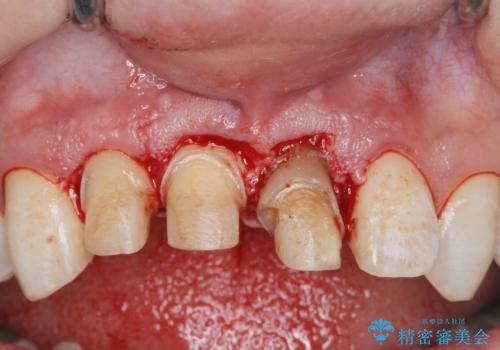

・歯肉縁下カリエス →部分矯正による歯の挺出・歯周外科

歯の挺出を行ったことで歯ぐきの腫れも改善され、安定した歯周環境下でのセラミッククラウン治療を行うことができました。